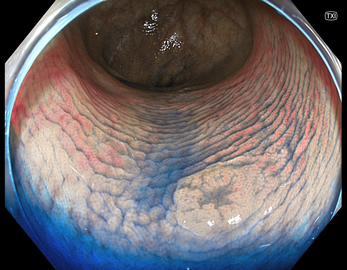

TXIは、「画像の構造を強調する」技術です。これは特別に目新しいものではありません。パソコンの画像編集ソフトや、スマホのアプリでも御馴染みの技術です。しかし、「どのような構造強調が実際に、内視鏡に一番、合うか?(強すぎると不自然になる!)」は、難しい(アナログ的な)課題です。オリンパス社は数タイプのTXIモードを用意しました。半年間の試行錯誤の末、今では下記のモードがベストと判断しました。そして今では「TXI無しの内視鏡は不要(フルタイムTXI)」というまで常用しています。

写真だけ、見ると「言われてみるとTXIの方が認識しやすい。でも僅かの差」と感じるでしょうが、この「僅かの差」が、人間の脳での検出には大きな差になります。青い色素(インジゴ・カルミン)が非常に強調され、粘膜の凸凹が明瞭になるのが特徴です。

通常観察 TXIモード

青い色素は追加していません![]()